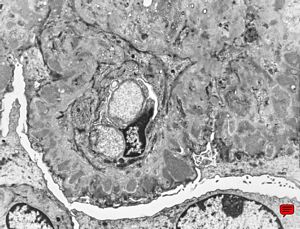

M,13y. | type III membranoproliferative glomerulonephritis

type III membranoproliferative glomerulonephritis